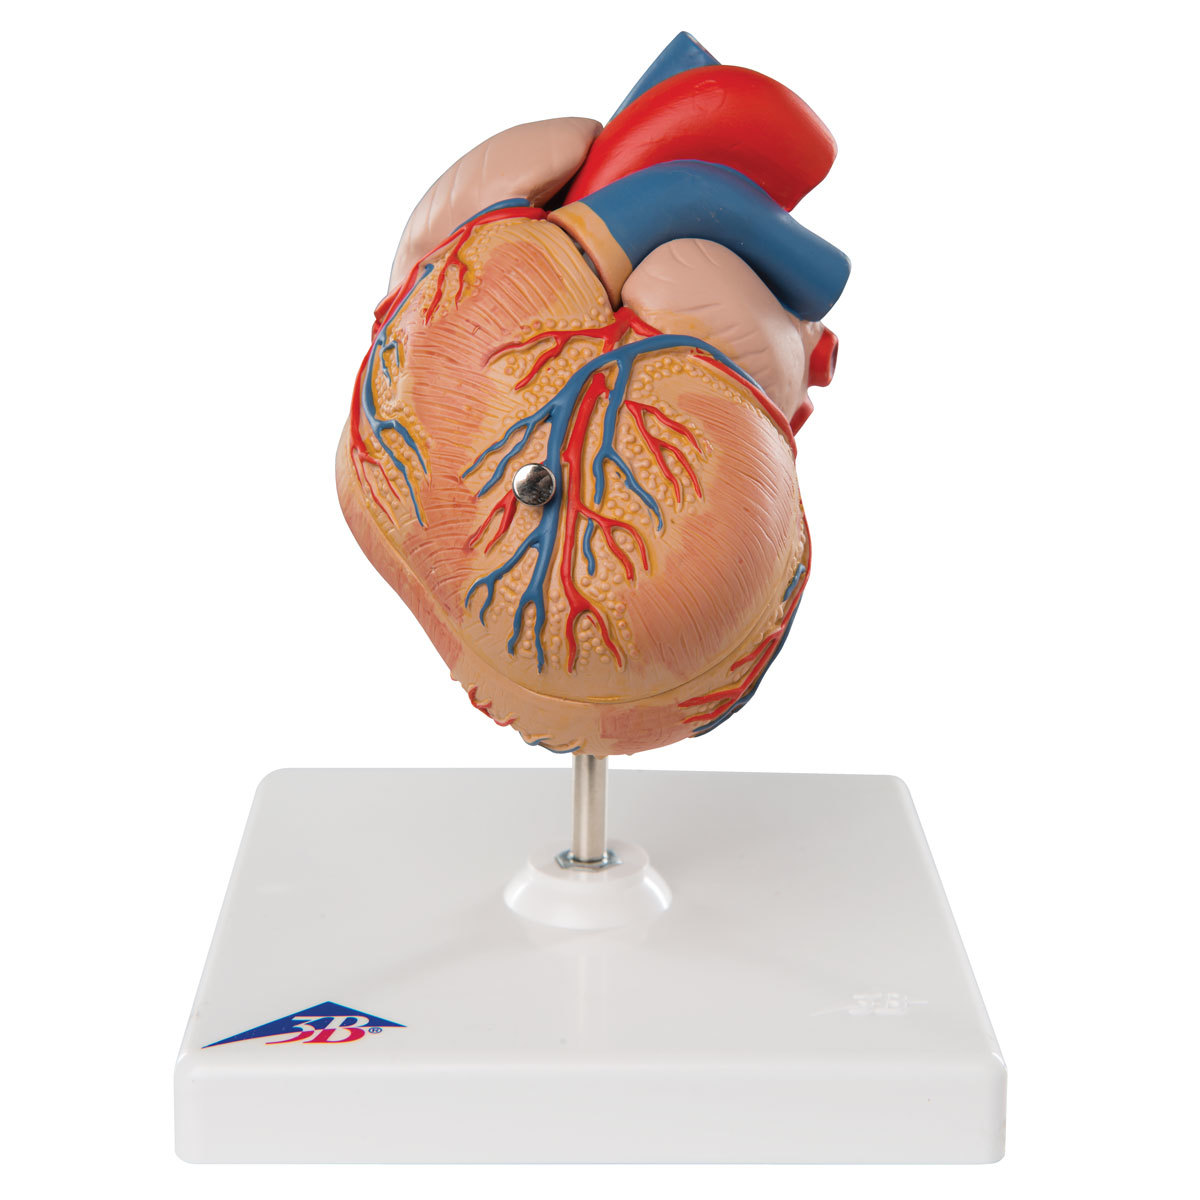

Фотографии и 3D-модели анатомии сердца человека